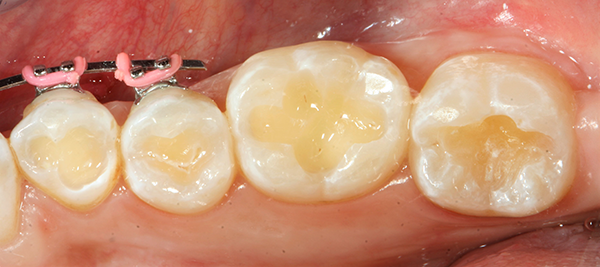

A 25-year-old female presented to the office with complaints of staining on her posterior teeth and sensitivity to sweets. Upon clinical and radiographic exams, decay was diagnosed in the occlusal grooves of most of her posterior dentition.

The following treatment sequence depicts one quadrant of her restorations. The teeth addressed were teeth #18-21.

After local anesthetic was administered, all visible decay was removed (Fig. 1) and, following the latest Dental Caries 2018: New Insights recommendation, all “affected” dentin layers were also removed. The preparation was disinfected with 5 percent gluteraldehyde-35 percent hydroxylethyl methacrylate (HEMA) formulations applied with Ball-Point Applicators™by KaVo Kerr.

Fig. 1 Fig. 2

After the two separate one-minute applications of disinfectant, the restorations were suctioned to achieve a damp surface.2 This step was followed by the application of OptiBond™ All-In-One self-etching dental adhesive by KaVo Kerr with Ball-Point Applicators (Fig 2 ).